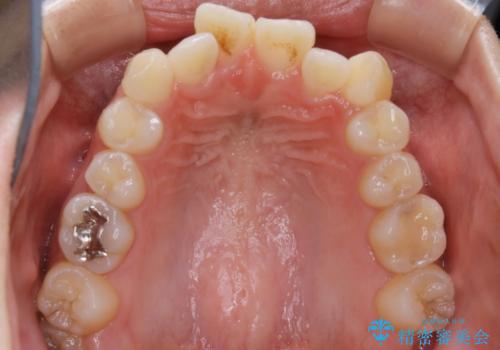

- 上下の歯のガタつきを主訴にご来院されました。

前歯部に特にガタつきが見られ、正中もズレている状態でした。

矯正装置の希望がインビザラインだったため、マイクロインプラントを併用し、奥歯から順に遠心移動をかけていくことにより非抜歯でも主訴のガタつきを治すことができました。

マウスピースとマイクロインプラントを組み合わせることで、抜歯をしなくても歯並びを治すためのスペースを作ることができます。奥歯から順に移動させていくので前歯に変化が出るまでには時間がかかりますが、その分健康な歯を抜歯することなく理想的な歯並びを手に入れることができます。